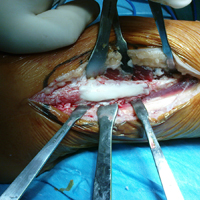

• Οστεολυτική εξεργασία περόνης